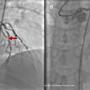

Defying All Odds: Successful Thrombolysis in a Nonagenarian with Posterior Circulation Infarct